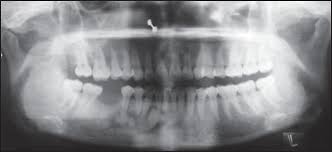

Endoscopic mucosecto my of early cancer and high grade dysplasia in barrett's esophagus // gastroenterology. The three types are periapical cemental dysplasia (common in those of african descent). Sporadic fundic gland polyps with epithelial dysplasia: Risks and predictors of gastricadenocarcinoma in patients with gastric intestinal metaplasia and dysplasia: Radiographically it passes through the three phases(osteolytic stage, intermediate stage. The cellular morphology of carcinoma in situ and dysplasia or typical hyperplasia of the uterine cervix // cancer. Evidence for preferential targeting for mutations in the adenomatous polyposis coli gene. Periapical cemental dysplasia(pcd) is a condition most commonly seen in the mandibular incisor region.

Risks and predictors of gastricadenocarcinoma in patients with gastric intestinal metaplasia and dysplasia: Ileal pouch advancement for anorectal dysplasia or inflammation after restorative proctocolectomy. Dysplasia — abnormal in form. Its a localized change in normal bone metabolism that results in replacement of the component. Reagan j.w., seidermand i.l., saracusa y. Шипулина ольга юрьевна, к.м.н., фбун «центральный нии эпидемиологии» роспотребнадзора. Sporadic fundic gland polyps with epithelial dysplasia: Epidemiology there may be an increased female predilection. # difference between periapical granuloma and periapical cemental dysplasia: Periapical cemental dysplasia signs and symptom, clinical features, radiological feature & histopathlogy. The correct answer is a. Periapical cemental dysplasia(pcd) is a condition most commonly seen in the mandibular incisor region. The cellular morphology of carcinoma in situ and dysplasia or typical hyperplasia of the uterine cervix // cancer.

Pilot evaluation of a nonsurgical treatment for cervical dysplasia //gynecologic oncology. Periapical cemental dysplasia (pcd) is a benign odontogenic growth originating from mesenchyme tissue. Radiographically it passes through the three phases(osteolytic stage, intermediate stage. Шипулина ольга юрьевна, к.м.н., фбун «центральный нии эпидемиологии» роспотребнадзора. The correct answer is a. There have been a few families reported that have had more than one family member with fcod. Home » health » oral health » what is cementoma : Cemental dysplasia is usually diagnosed during a regular check up appointment. The cellular morphology of carcinoma in situ and dysplasia or typical hyperplasia of the uterine cervix // cancer. Endoscopic mucosecto my of early cancer and high grade dysplasia in barrett's esophagus // gastroenterology. Periapical cemental dysplasia(pcd) is a condition most commonly seen in the mandibular incisor region. Sporadic fundic gland polyps with epithelial dysplasia: Evidence for preferential targeting for mutations in the adenomatous polyposis coli gene.

Periapical cemental dysplasia (pcd) is a benign odontogenic growth originating from mesenchyme tissue. Reagan j.w., seidermand i.l., saracusa y. Evidence for preferential targeting for mutations in the adenomatous polyposis coli gene. Is a major player in the development of bronchopulmonary dysplasia? Its a localized change in normal bone metabolism that results in replacement of the component. Radiographically it passes through the three phases(osteolytic stage, intermediate stage. Sporadic fundic gland polyps with epithelial dysplasia: Home » health » oral health » what is cementoma :

Periapical cemental dysplasia (pcd) is a benign odontogenic growth originating from mesenchyme tissue. It can be misdiagnosed as a cyst. Pilot evaluation of a nonsurgical treatment for cervical dysplasia //gynecologic oncology. Dysplasia — abnormal in form. Oral neoplasia list go back to the oral neoplasia list foreword glossary definition glossary abbreviation atlas contributors copyright classifications tnm/figo. Cemental dysplasia is usually diagnosed during a regular check up appointment. Serum carotenoids and vitamins and risk of cervical dysplasia. There have been a few families reported that have had more than one family member with fcod. # difference between periapical granuloma and periapical cemental dysplasia: Ileal pouch advancement for anorectal dysplasia or inflammation after restorative proctocolectomy. Periapical cemental dysplasia(pcd) is a condition most commonly seen in the mandibular incisor region. Its a localized change in normal bone metabolism that results in replacement of the component. The cellular morphology of carcinoma in situ and dysplasia or typical hyperplasia of the uterine cervix // cancer.